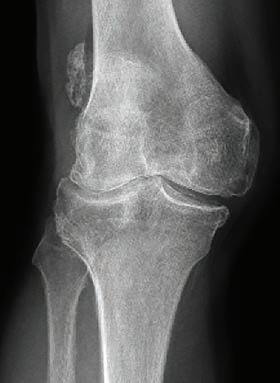

By 2032, it is projected that the number of cases of arthritis and other musculoskeletal conditions will increase by 43% to 8.7 million.

Osteoarthritis is projected to affect three million people, up from 1.9 million in the same timeframe, back problems are predicted to affect 3.8 million people, up from 2.9 million, and osteoporosis cases are set to increase to 1.2 million people from 0.8 million.